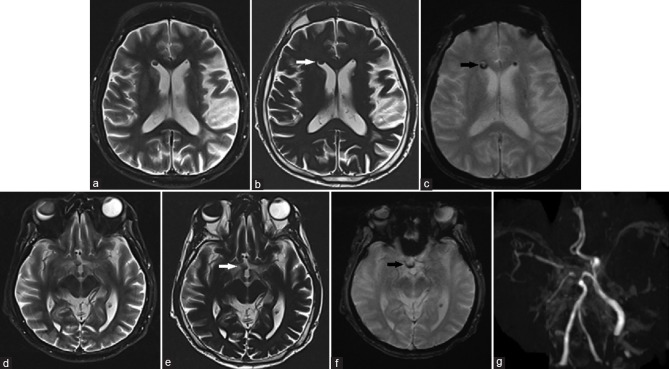

Intraventricular and subarachnoid migration of silicone oil from previous intraocular injection mimicking intracranial haemorrhage: a case report.